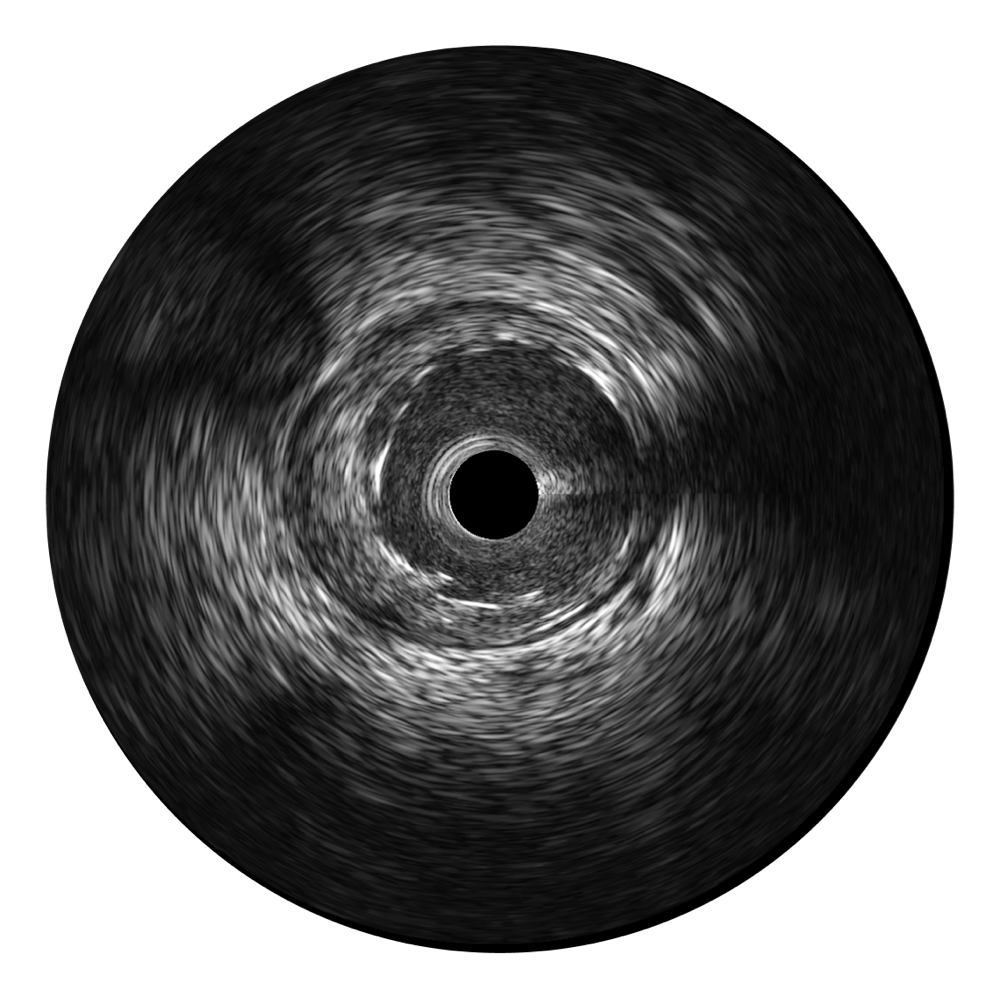

传统IVUS图像

对比传统IVUS导管成像,16877太阳集团宽频IVUS图像的近场支架梁显影更细腻,远场中膜外血管仍清晰可辨,兼顾远中近,兼顾分辨力与穿透深度